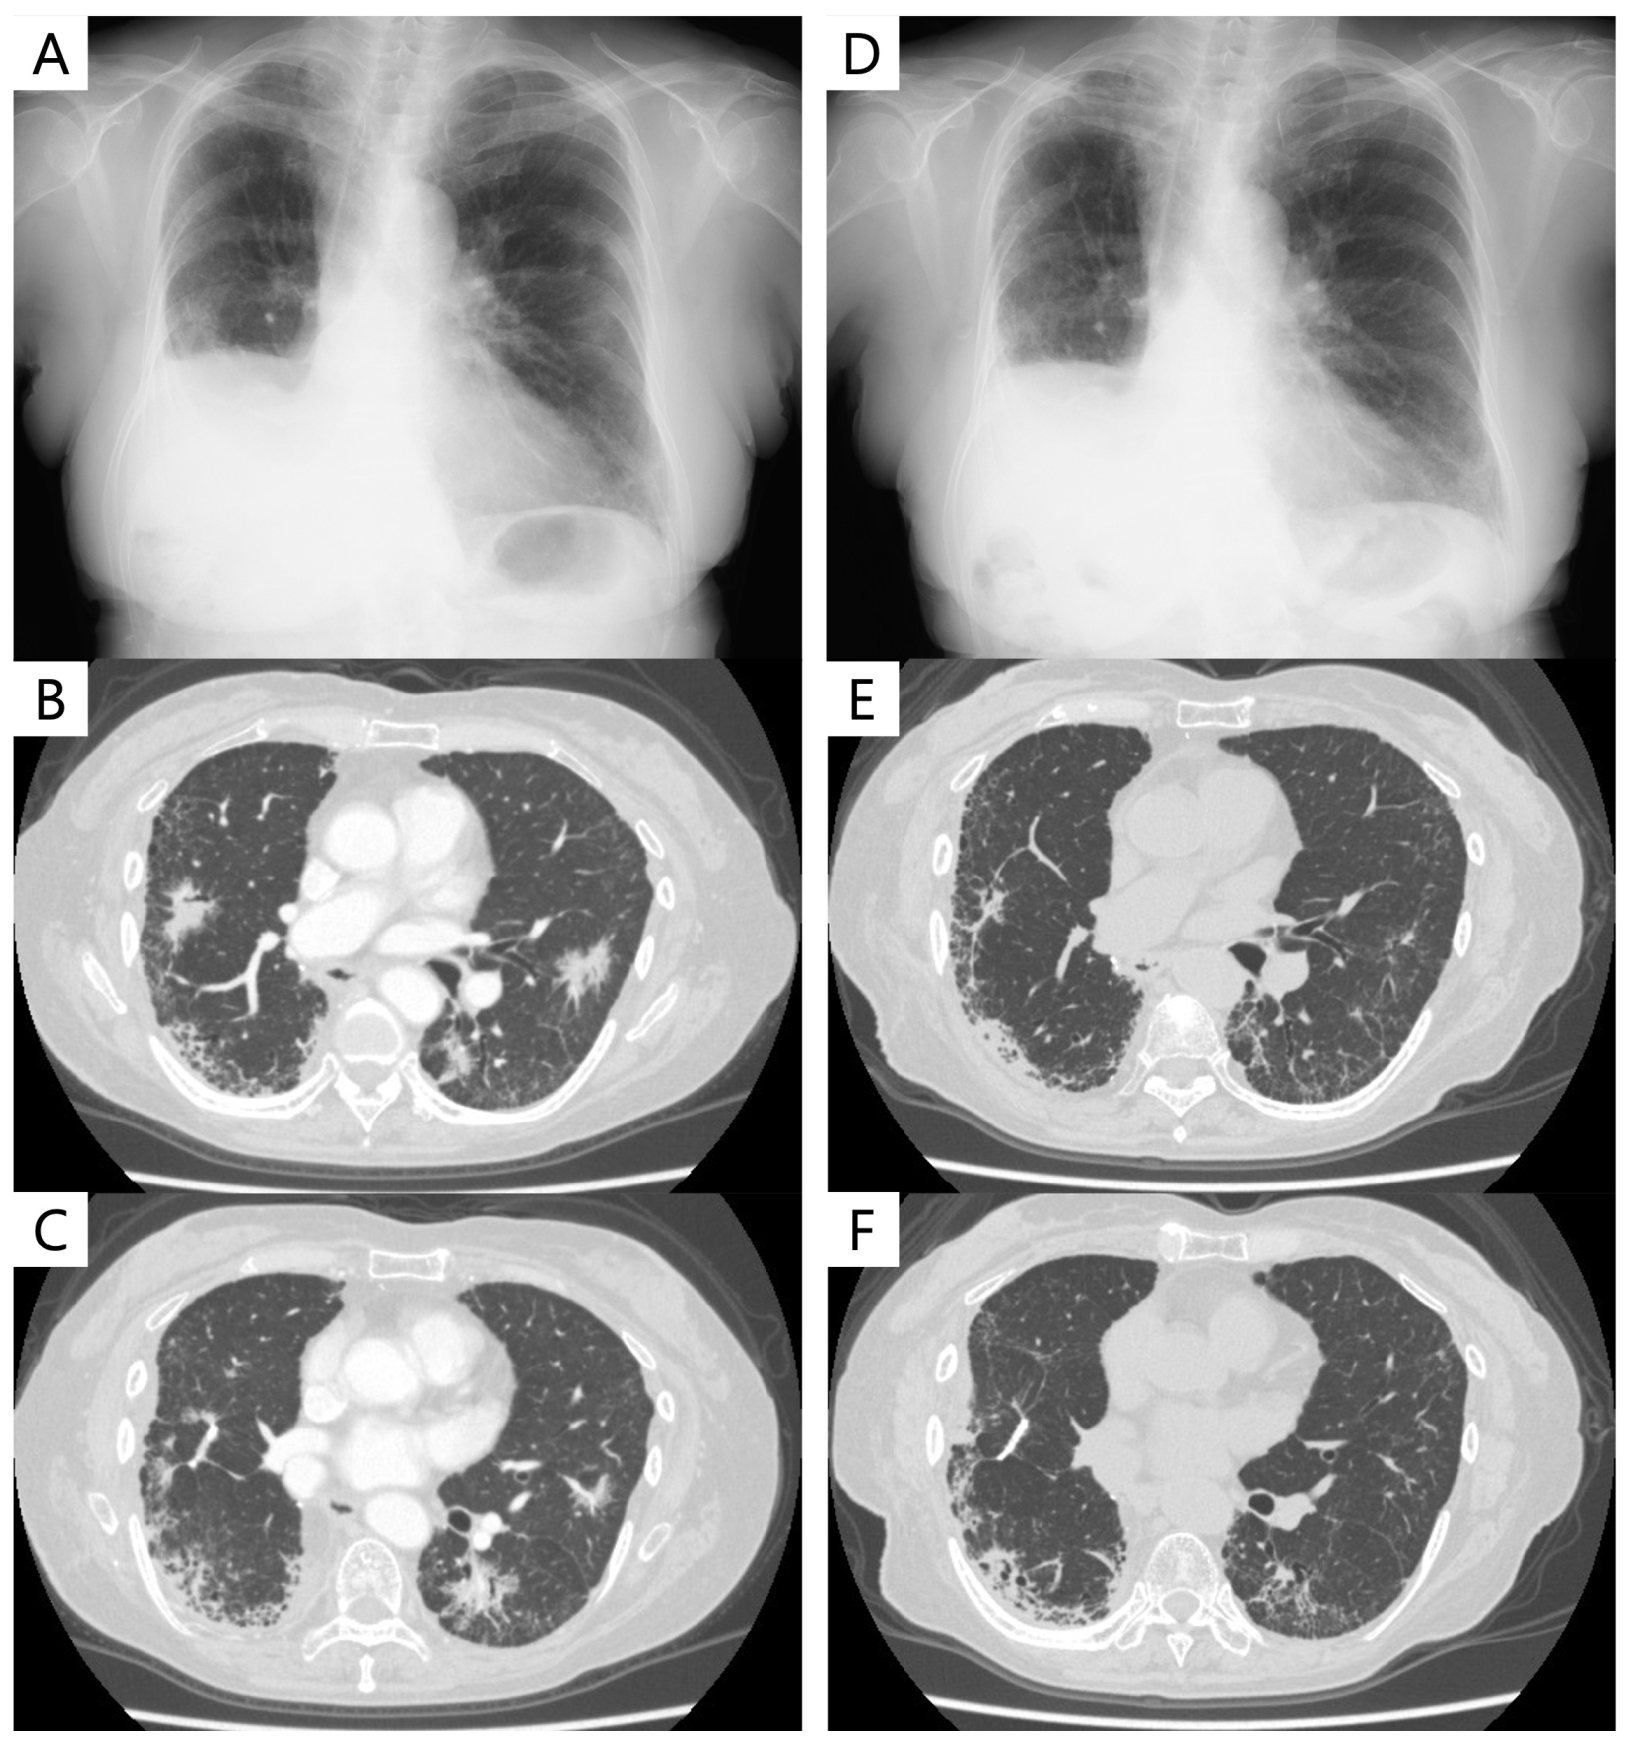

4.3. Case Presentation